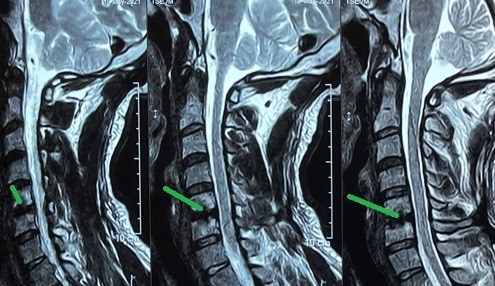

unilevel cervical herniated disc

Magnetic resonance imaging (MRI) of a 52-year-old female patient suffering from weakness and partial upper extremity weakness due to a herniated cervical disc between the fifth and sixth cervical vertebrae. As shown in red, the location of the slip and the size of the effect resulting from pressure on the cervical spinal cord and nerve roots. And the image shaded in green after a surgical microscope surgery to remove the cartilage from the front and install a cervical cage or an alternative anterior cervical brace, three months after the surgery.